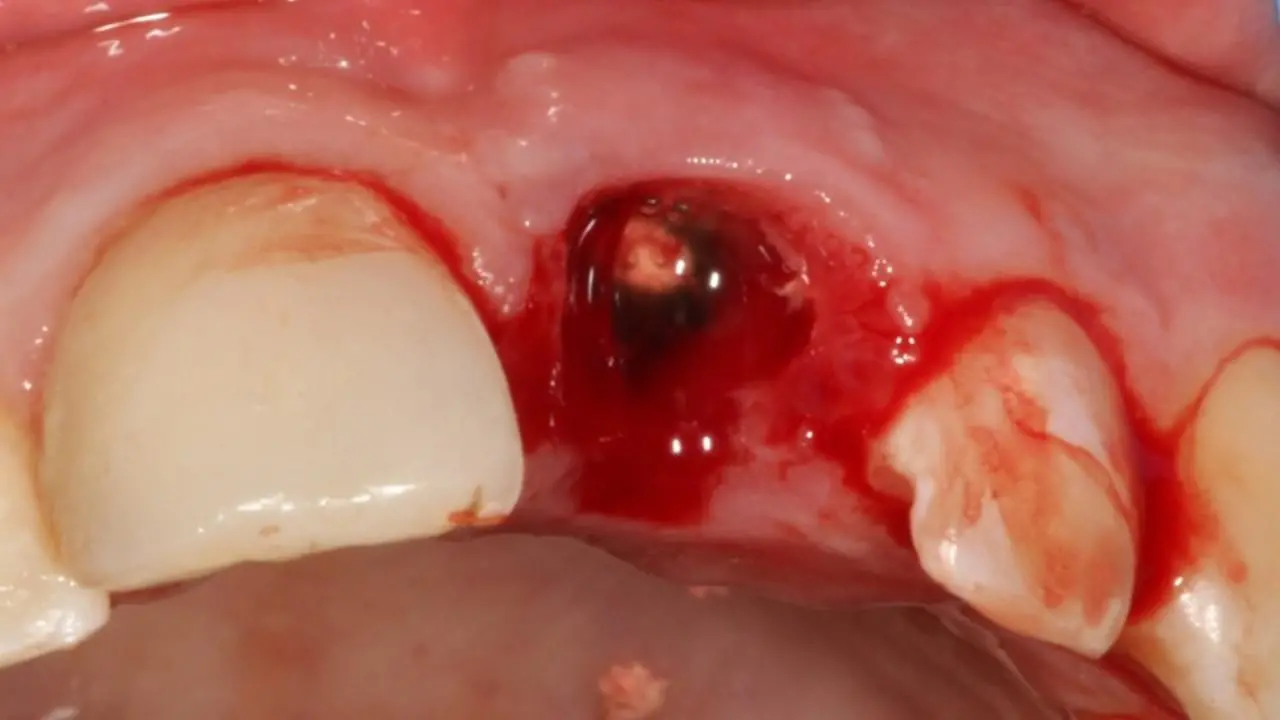

Коли лікар-стоматолог стикається з травмою постійного зуба у дитини, часто необхідно мобілізувати максимум знань і навиків: від реставрації до хірургії. Але найперше - це правильно визначити тактику. Наш курс допоможе відповідним чином приймати рішення в різних клінічних випадках травми постійних зубів у дітей. І не тільки приймати рішення, а і належно їх реалізувати в лікувальну тактику. На детальних клінічних прикладах ми демонструємо належну клінічну тактику та техніки, які часто допомагають врятувати постійні зуби юних пацієнтів.